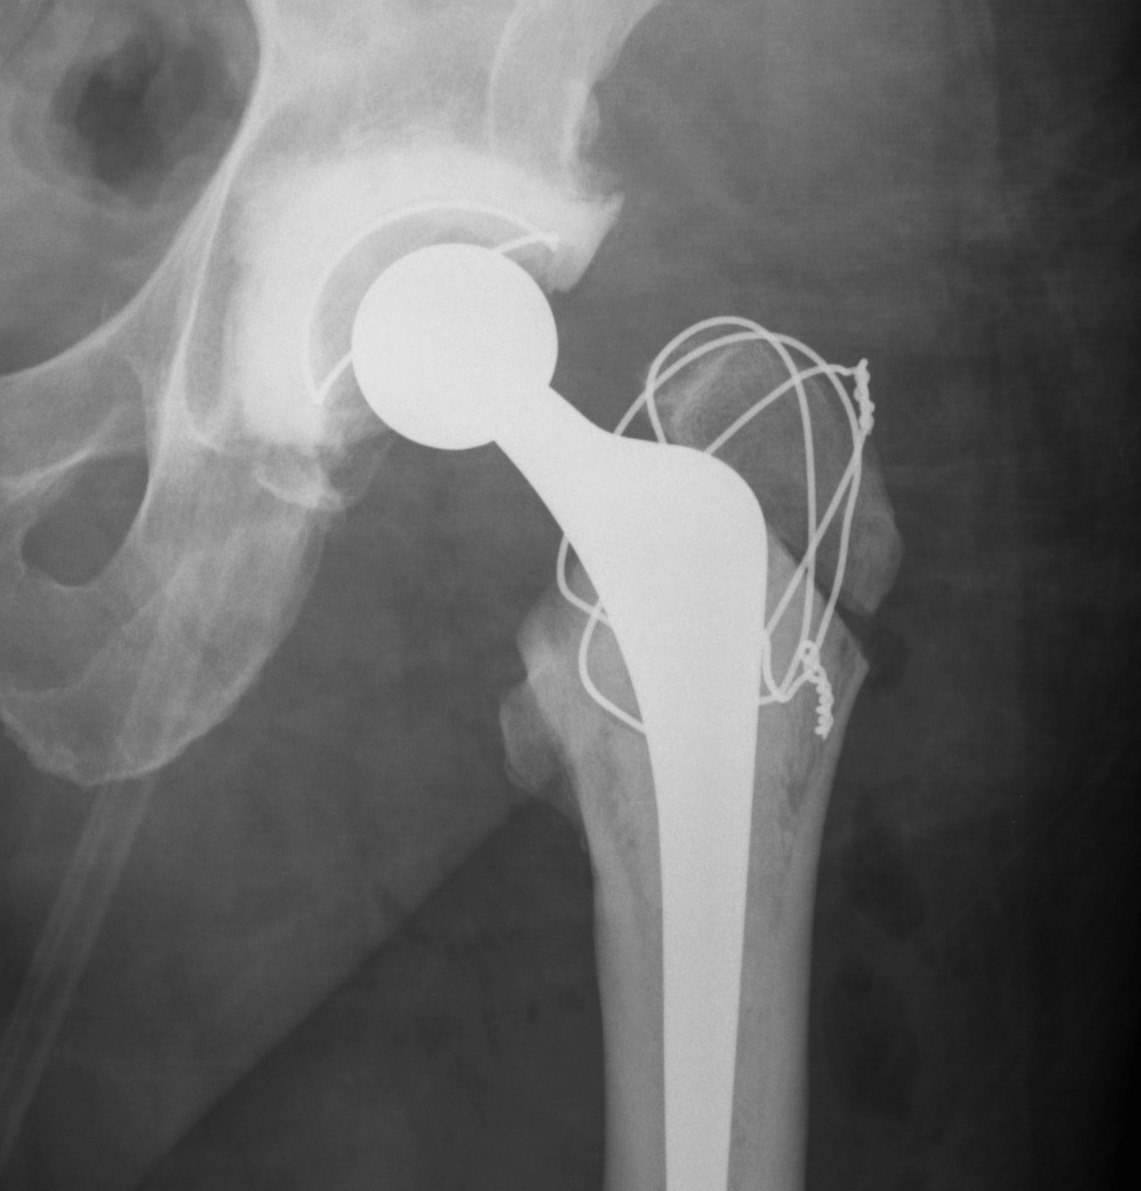

Extended Trochanteric osteotomy

Concept

Osteotomy lateral 1/3 to 1/2 of trochanter & femur

- posterior to anterior longitudinal cut

- short distal transverse cut

- levers / hinges open anteriorly

- maintains anterior vasculature / muscle attachment

Fixation

- 3 x cerclage cables

- protect sciatic nerve / palpate / pass wires posterior to anterior

- submuscular

Results

98 – 100% union rate by 6/12